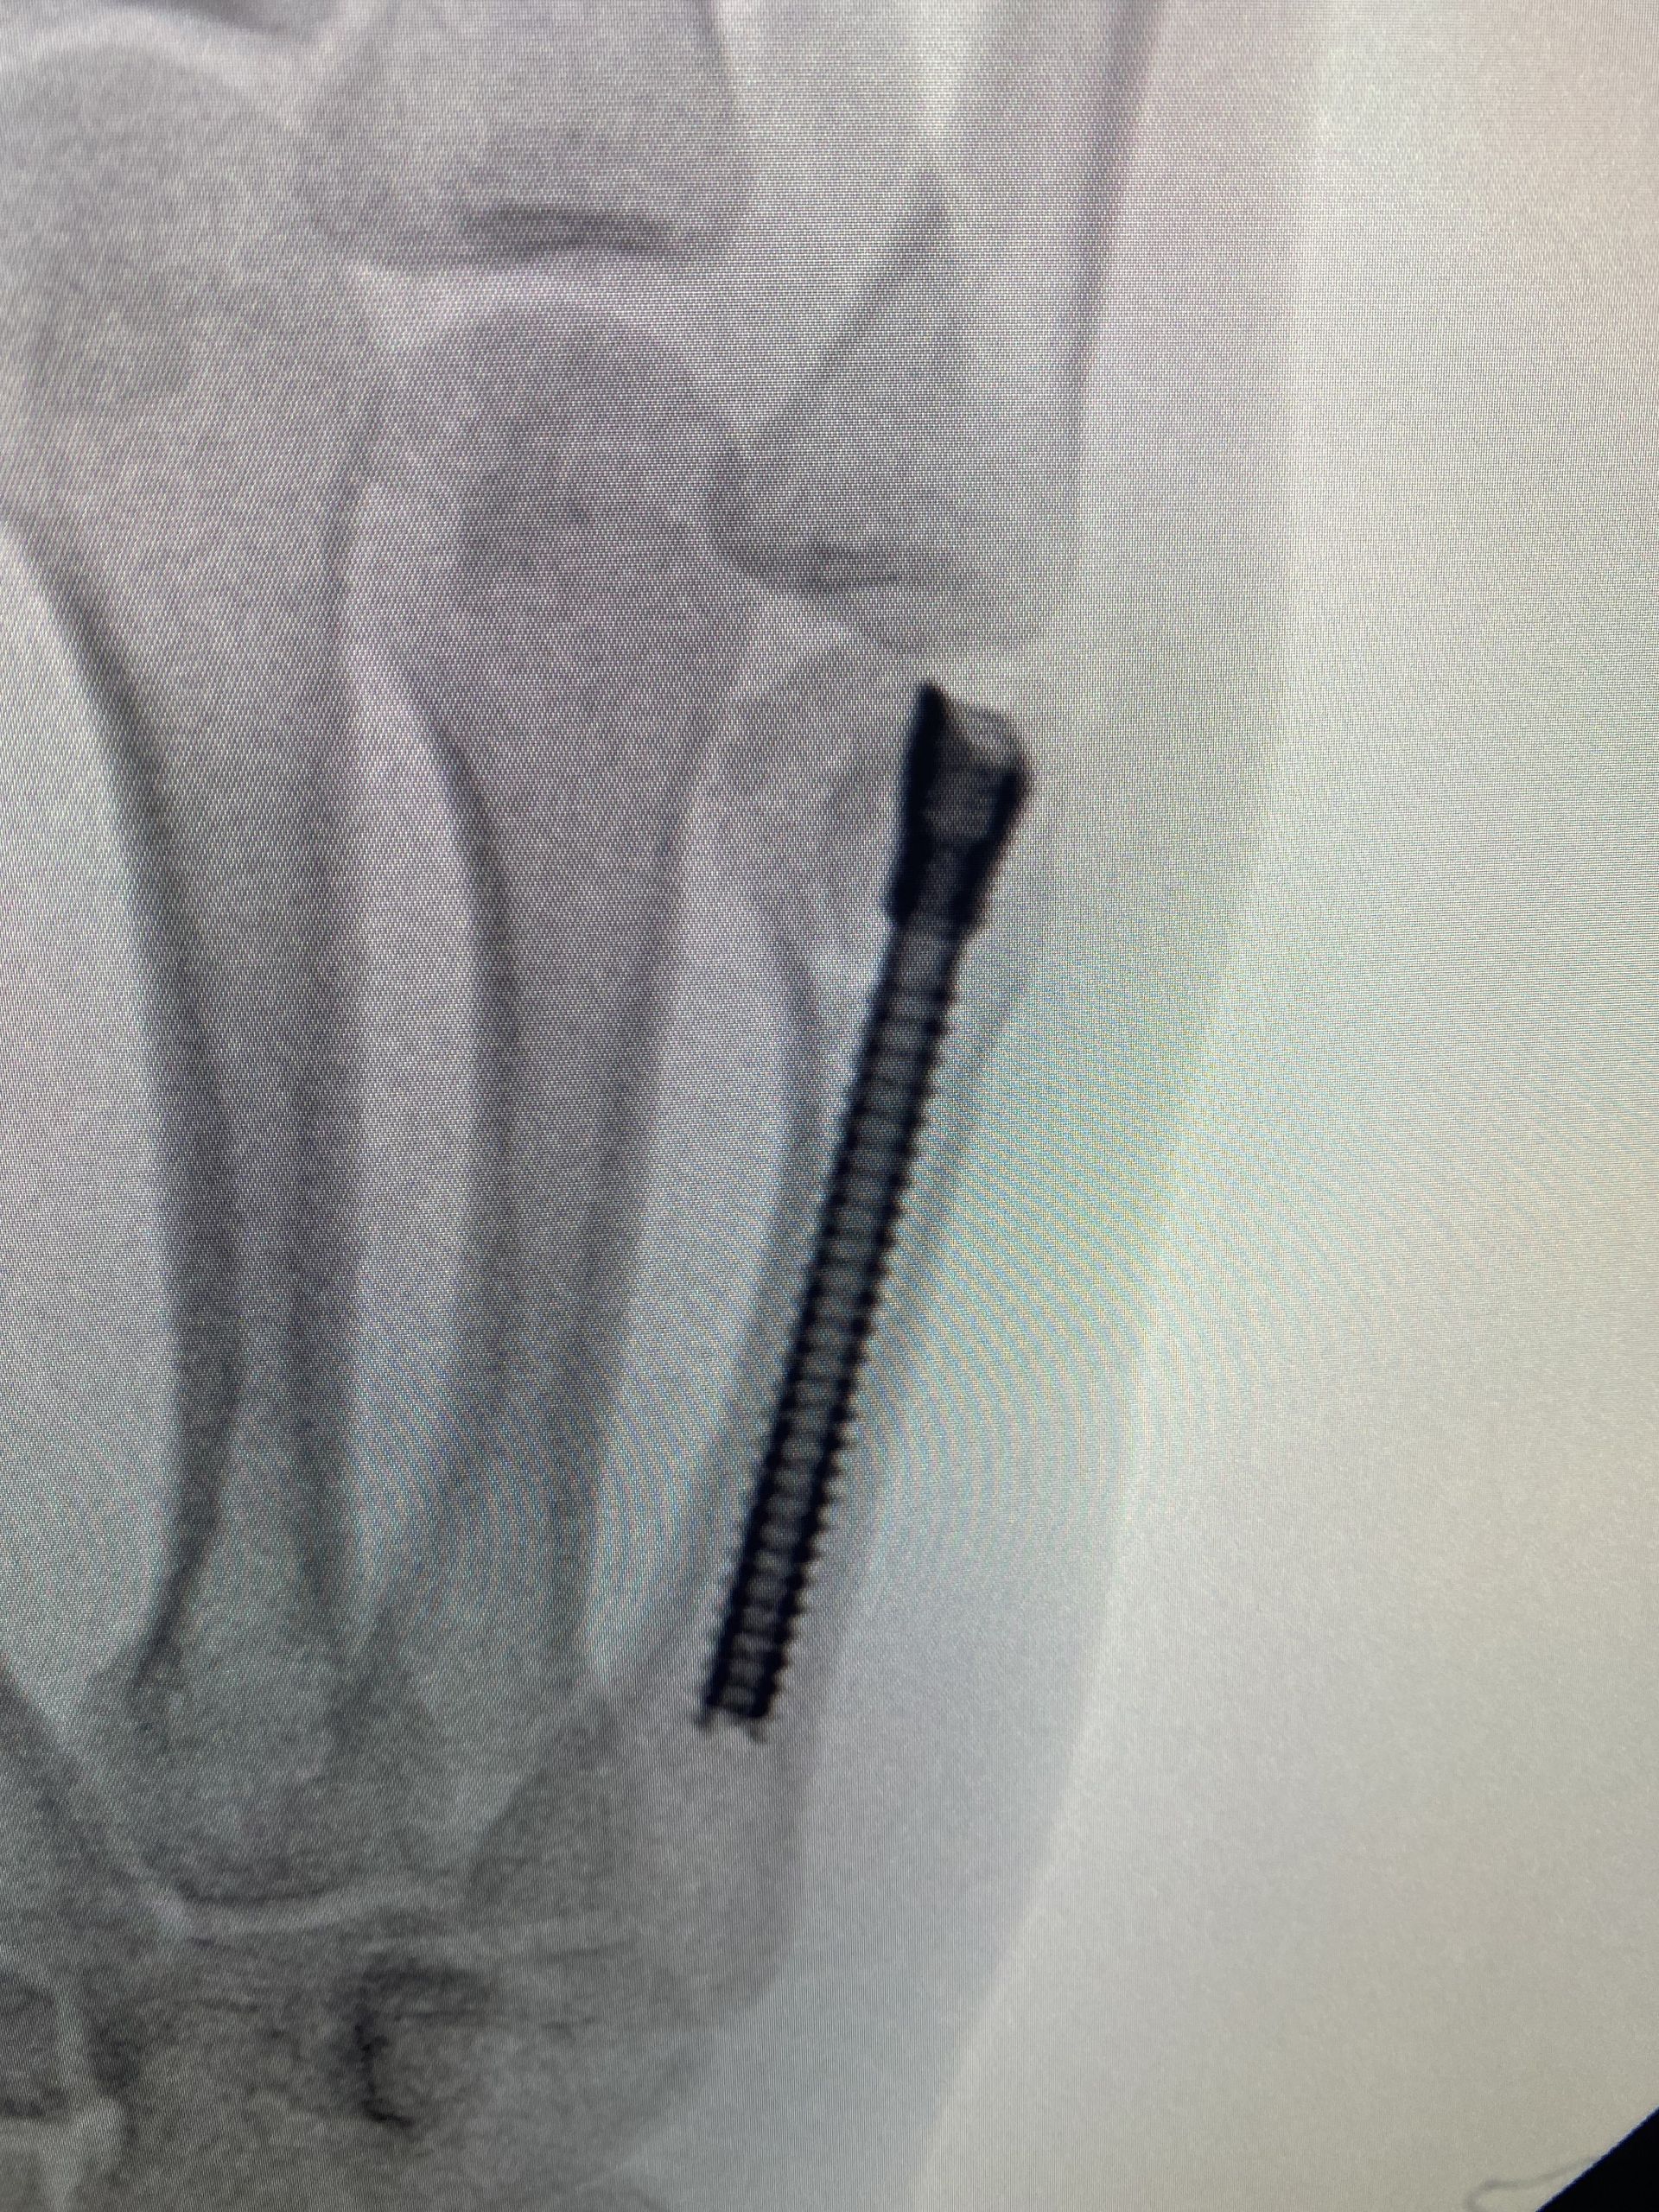

A técnica de parafuso intramedular é menos invasiva e foi descrita pela primeira vez em 2010, por Boulton et al. A técnica é minimamente invasiva e consiste em realizar uma incisão sobre o tendão extensor, no nível da articulação metacarpofalangeana, introduzir um fio guia e um parafuso intramedular de modo retrógrado. A fixação é rígida o suficiente para permitir movimentação ativa precoce, além de haver mínima dissecção de partes moles, menor risco de aderência tendínea, ausência de proeminência de material de síntese e ausência do risco de infecção das hastes expostas.

Em uma meta-análise realizada em 2019, Beck et al. avaliaram 169 pacientes e os resultados foram surpreendentes: 100% de união da fratura, 96% de recuperação de força de preensão palmar, 86° de flexão da articulação metacarpofalangeana e poucas complicações descritas. A crítica acerca de tal técnica cirúrgica é a violação articular por conta do acesso para introdução do parafuso. Mas a literatura não mostrou evidências de que esse ponto de introdução do parafuso traga malefícios ou prejuízos funcionais.

Em uma publicação de 2013, após análise tomográfica, foi comprovado que há apenas 12% de contato entre a base da falange proximal e o ponto de entrada do parafuso, dada a sua introdução dorsal (mesmo com a articulação metacarpofalangeana em completa extensão).

Sequência de imagens evidenciando fratura de colo do 5° metacarpo, desvio rotacional do 5° raio, redução da fratura com uso de parafuso intramedular (3 incidências intraoperatórias) e resultados clínicos no 5° dia pós operatório. O processo de reabilitação precoce permitiu que o paciente retomasse suas funções laborais e esportivas de modo mais rápido. Evoluiu com recuperação total da amplitude de movimento, força de preensão palmar e destreza para tocar seus instrumentos musicais.